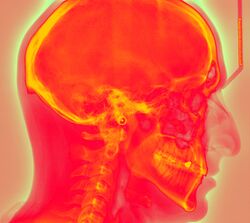

Photostimulated luminescence (PSL) is the release of stored energy within a phosphor by stimulation with visible light, to produce a luminescent signal. X-rays may induce such an energy storage. A plate based on this mechanism is called a photostimulable phosphor (PSP) plate and is one type of X-ray detector used in projectional radiography. Creating an image requires illuminating the plate twice: the first exposure, to the radiation of interest, "writes" the image, and a later, second illumination (typically by a visible-wavelength laser) "reads" the image. The device to read such a plate is known as a phosphorimager (occasionally spelled phosphoimager, perhaps reflecting its common application in molecular biology for detecting radiolabeled phosphorylated proteins and nucleic acids). Projectional radiography using a photostimulable phosphor plate as an X-ray detector can be called "phosphor plate radiography"[1] or "computed radiography"[2] (not to be confused with computed tomography which uses computer processing to convert multiple projectional radiographies to a 3D image).

Computed radiography is used for both industrial radiography and medical projectional radiography. Image plate detectors have also been used in numerous crystallography studies.[5]

In phosphor plate radiography, the imaging plate is housed in a special cassette and placed under the body part or object to be examined and the x-ray exposure is made. The imaging plate is then run through a special laser scanner, or CR reader, that reads and converts the image to a digital radiograph. The digital image can then be viewed and enhanced using software that has functions very similar to other conventional digital image-processing software, such as contrast, brightness, filtration and zoom. CR imaging plates (IPs) can be retrofitted to existing exam rooms and used in multiple x-ray sites since IPs are processed through a CR reader (scanner) that can be shared between multiple exam rooms.[6]